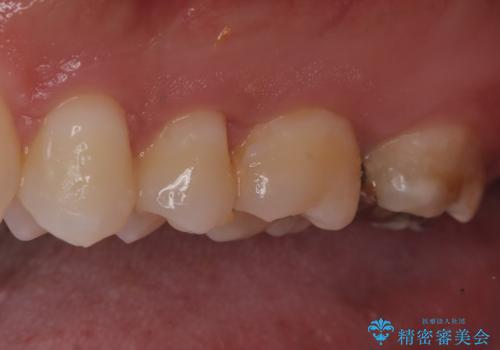

- 定期健診にて虫歯を見つけたためセラミックインレーにて修復しました。

綺麗に仕上がり患者さんも非常に満足されていました。

当院でのセラミックインレーはラバーダム防湿をして接着しております。